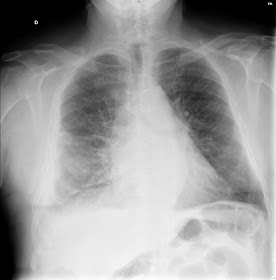

Recientemente se ha señalado la posibilidad de que exista una forma grave en pacientes con un área valvular aórtica < 1 cm2 denominada EA paradójica de flujo y gradientes bajos (volumen de eyección indexado < 35 ml/m2 y gradiente medio < 40 mmHg respectivamente) con Fracción de eyección del ventrículo izquierdo (FEVI) preservada, cuya valoración requiere mayores pruebas diagnósticas complementarias, como son la ecocardiografía de estrés con dosis bajas de dobutamina, la tomografía computarizada multicorte (TCMC), la ecocardiografía transesofágica, la angiografía por radionucleótidos o la resonancia magnética nuclear (RMN).La radiografía de mi paciente con insuficiencia cardiaca era la siguiente:

Además

de los datos de insuficiencia cardiaca, podía ver, sobre todo en la

placa lateral del tórax, una imagen de un objeto metálico situado

donde anatómicamente le corresponde estar a la válvula aórtica y

que no era ninguna de las prótesis metálicas que conozco desde que

estudié medicina, hace ya años.

Ahora

sí, ya podemos decir que la imagen de la radiografía de mi paciente

correspondía a una de estas nuevas válvulas biológicas sin sutura

que tienen una parte metálica

En concreto, la imagen corresponde a una prótesis Perceval que está compuesta por una válvula de pericardio bovino montada sobre un armazón o stent de nitinol (aleación metálica de niquel y titanio), que es lo que se ve en la radiografia.